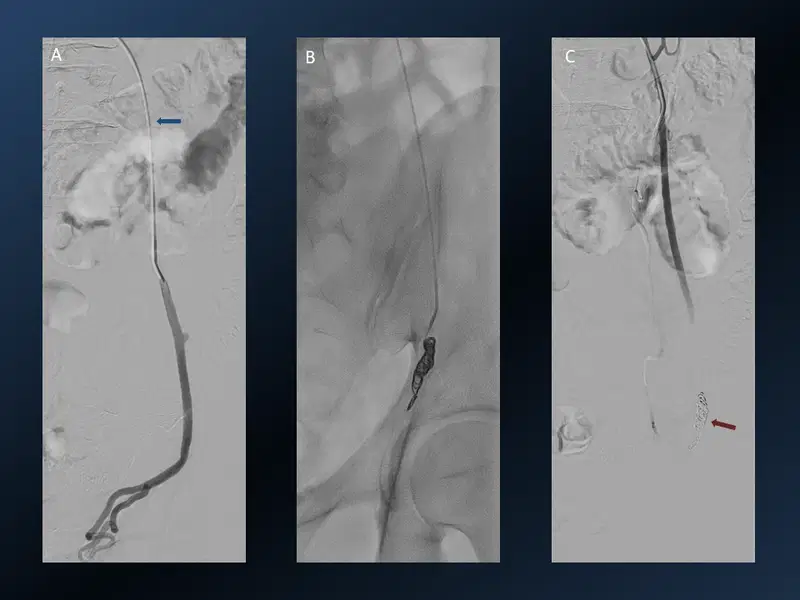

16. Varicoele Embolisation

Varicoele Embolisation Interventional Radiology

Young patient with long standing left testicular dragging pain and discomfort. Left testicular vein was cannulated (blue arrow) via brachial access and a venogram on Valsalva manoeuvre demonstrated reflux (A). Coils (red arrow) in the pelvic segment of left testicular vein (B&C). Post embolization stasis with no reflux on Valsalva (C).